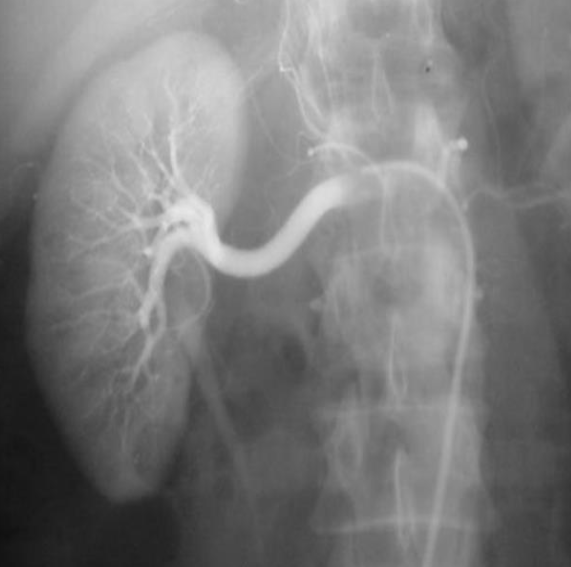

Renal arteriogram

Anatomy ?